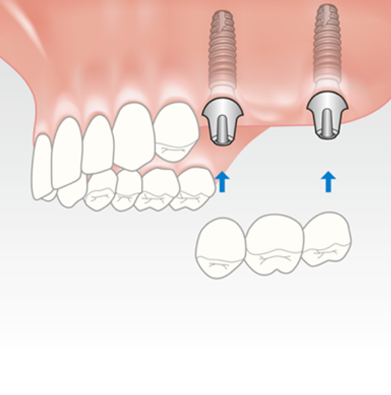

FULL ARCH DENTAL IMPLANT

Extensively damaged or missing teeth can not only impede you from living a fulfilling life but can also affect your health and confidence. But full arch mouth reconstruction solution, using implants can be used to support ill-fitting dentures or restore the entire arch with a bridge to improve appearance and reinstate complete oral functions.

4-6 implants are placed in each jaw an aesthetic, functional bridge is fabricated over the implants. It need not be removed to clean on a daily basis and is probably the closest to natural teeth in function and aesthetics.

2-4 implants are placed in the lower jaw, 4-6 implants in the upper jaw can support a full denture. This procedure is very economical, greatly improves retention, stability and function. All of these stages can be carried out in the single appointment depending on need and condition of the patient.

IMPLANT SUPPORTED BRIDGE

Card image Actual Practice Photographs ©Dr.Pavan Bopanna